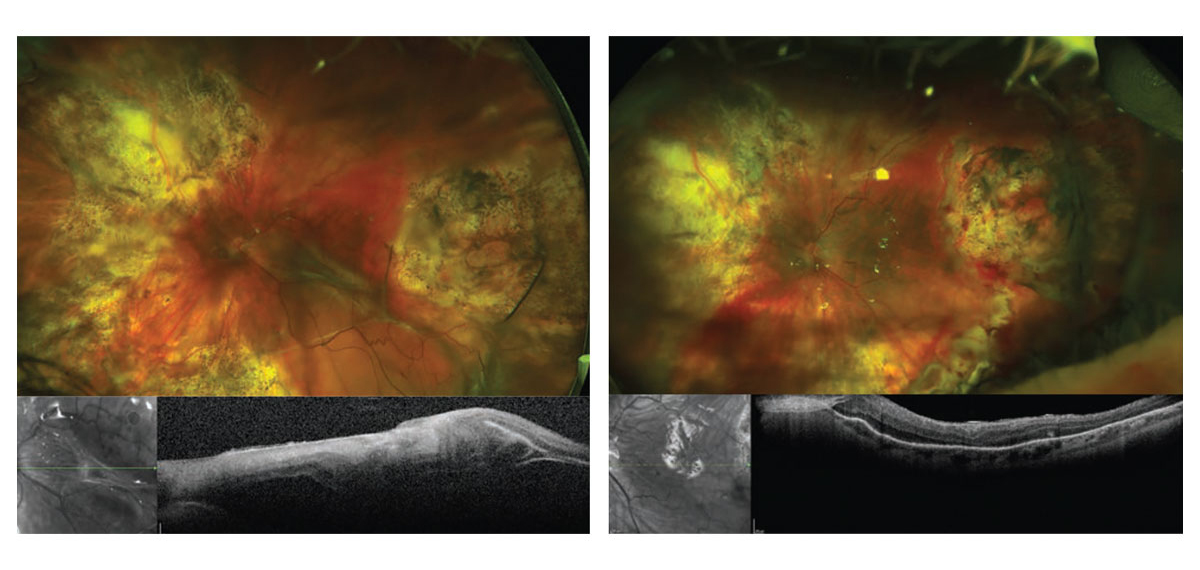

Read moreDetailsTerapias actuales para la PVR

Aunque se han estudiado diversas opciones terapéuticas, la cirugía sigue siendo la única manera eficaz de...